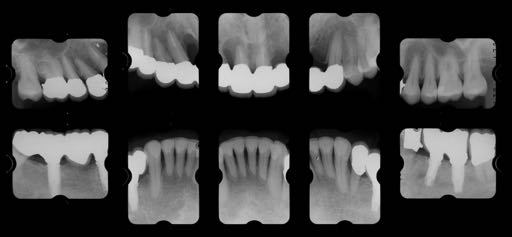

治療後01

治療後02

治療後03

治療後04

治療後05